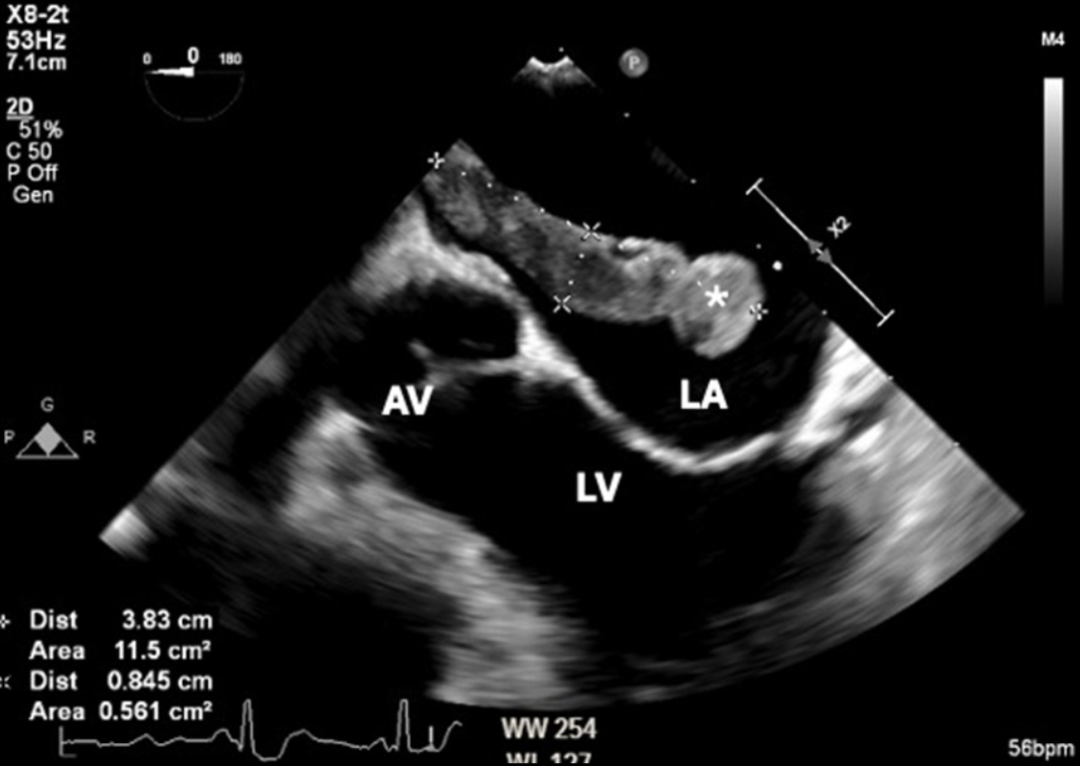

术中经食管超声心动图证实存在一个穿过PFO的大血栓(图 3、图 4)。患者随后接受急诊肺动脉取栓术+心房血栓清除术+PFO封堵术。

图 3 术中经食管超声心动图显示左心房内大血栓(*),突向二尖瓣(LA:左房,LV:左室,AV:主动脉瓣)。